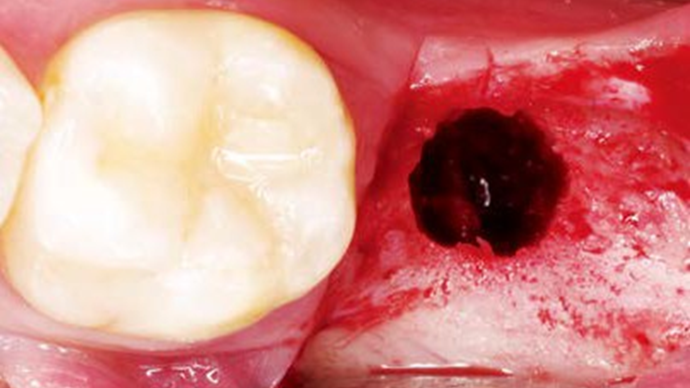

Clinical case: Bone filling into the bottom of deepest thread at 8.0mm AnyRidge fixture

- Courtesy of Dr. Kwang Bum Park -

AnyRidge, Knifethread ,extraction socket, ,initial stability ,Allograft, ,osseointegratio ,Dr. Kwang Bum Park, , Mandibular, Single replacement, AnyRidge, Mega-oss,

Implant system-AnyRidge, Regeneration-Mega-Oss